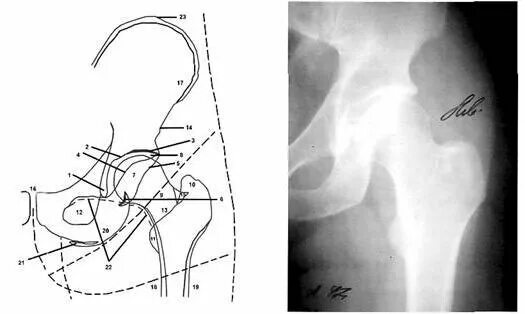

Проекции рентгена тазобедренного сустава